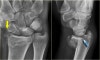

X-ray : 원위 요골 골절(Volar-type Barton's fracture)

X-ray : 원위 요골 골절(Dorsal-type Barton's fracture)

3. Barton 골절 : 관절 속의 골절로써 손목뼈가 손등이나 손바닥 쪽으로 아탈구됩니다(Volar-type : A fracture-dislocation of radial volar rim(m/c), Dorsal-type : A fracture-dislocation of radial dorsal rim).